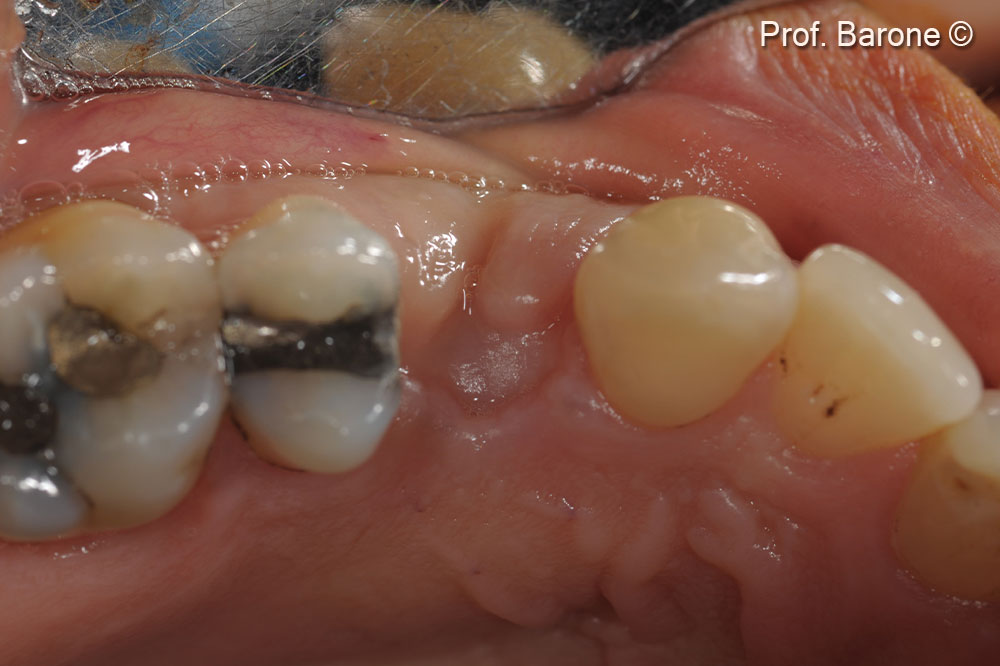

Clinical pre-operative lateral view of the tooth #24 (gingival recession and a fistula can be observed)